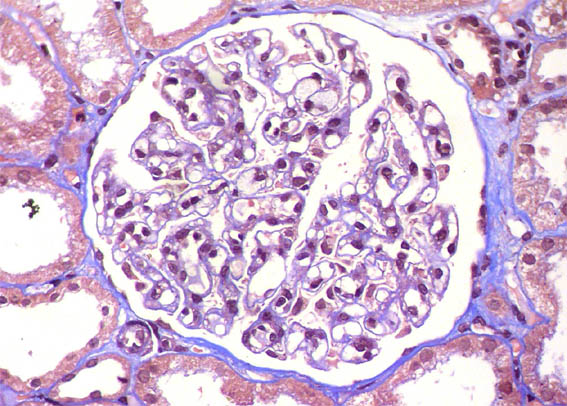

Figure 7. Masson's trichrome, X400.